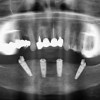

Per raggiungere risultati d’eccellenza è necessario avvalersi di materiale di qualità: per questo utilizziamo impianti NOBEL BIOCARE: leader mondiale nell’implantologia tanto da garantire a vita i propri impianti.

Altri marchi utilizzati, a seconda dei casi, sono:

- Impianti Exacta WP e NP- Biaggini Medical Devices

- Impianti Lodi – ZEST (Biomet 3i) nei casi di Overdentures.